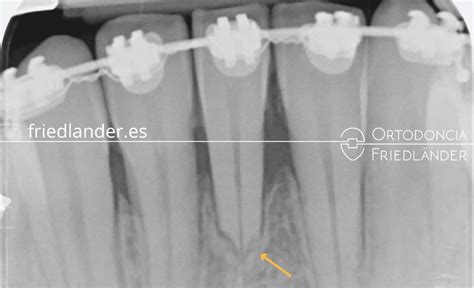

Diagnóstico

El diagnóstico de la rr en Ortodoncia se realiza mediante unas radiografías antes, durante y al final del tratamiento, una vez colocada la aparatología es aconsejable comprobar que no se esté produciendo rr. En aquellos dientes de riesgo aumentado, como ápices romos o en forma de pipeta, se recomienda el estudio radiográfico cada tres meses. Para comparar las distintas radiografías, éstas han de ser tomadas mediante la misma técnica radiográfica y con un método estandarizado, pues sólo así el cotejo es fiable.

La radiografía es la herramienta más usada para el diagnóstico de la reabsorción radicular, en particular las radiografías periapicales y las panorámicas, pero estas técnicas tienen limitaciones que no se deben pasar por alto. Las radiografías panorámicas sobreestiman la reabsorción radicular apical en un 20% cuando se comparan con las radiografías periapicales, y éstas a su vez la subestiman, al compararlas con la microtomografía. Las exploraciones con CBCT proporcionan imágenes tridimensionales de los dientes más precisas que las radiografías con vencionales. Sin embargo, como modalidad de examen, el CBCT debe usarse con precaución, ya que la dosis efectiva del CBCT puede ser entre 1,5 y 33 veces más alta que la asociada con las radiografías panorámicas.

Grados de Severidad

Se distinguen cuatro grados de severidad: en el grado 1 se observa un contorno radicular irregular, en el grado 2 hay un acortamiento no superior a 2mm de la longitud radicular, en el grado 3 la rr es aproximadamente de 2mm o 1/3 de la longitud radicular, y en el grado 4 la pérdida radicular es superior a 1/3 de la raíz. Sin duda, el grado 4 es el que peor pronóstico tiene según la clasificación de Levander (1988).